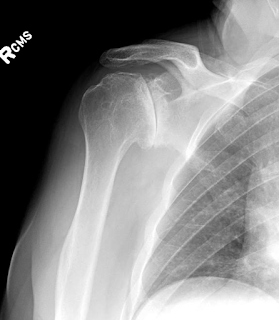

This patient presented with a chronic anterior dislocation of the humeral head after a proximal humerus fracture, the humeral head was malunited in the subscapularis recess. Osteotomy of the humeral head was required to remove the bone from the anterior glenoid. The fracture was addressed with hemiarthroplasty and repair of the tuberosities. The use of a stem that provides a "window" for proximal bone grafting, the removal of the cement circumferentially from the proximal stem during implantation, and the stable suture repair of the tuberosities with Fiberwire provided a good outcome with union of the tuberosities. The anterior inferior subluxation of the humeral head persisted for 6 months but eventually it was resolved. Contrary to the belief that this is the result of a "fracture hematoma" it seems that this finding is associated with muscle atony or contusion of the rotator cuff or axillary nerve neuropraxia. X-rays are shown below.